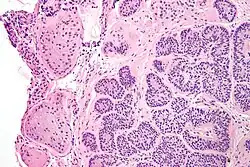

Micrograph of a Sertoli cell nodule. H&E stain.

A Sertoli cell nodule is a benign proliferation of Sertoli cells that arises in association with cryptorchidism (undescended testis).[1] They are not composed of a clonal cell population, i.e. neoplastic; thus, technically, they should not be called an adenoma.[2]

Sertoli cell nodules are unencapsulated nodules that consist of:[2][3][4]

1. cells arranged in well-formed tubules (that vaguely resemble immature Sertoli cells), with

2. bland hyperchromatic oval/round nuclei that are stratified, and

3. may contain eosinophilic (hyaline) blob in lumen (centre).